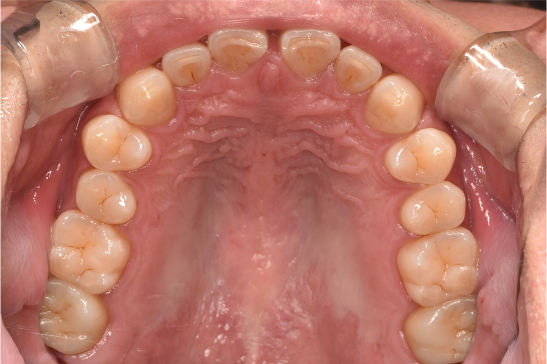

general 30代男性「タバコのヤニが気になる」縁上歯石・着色を除去し、その後歯周治療を行った症例

治療前

| カウンセリング・診断結果 | こちらの患者様は1日20本ほどタバコを吸われる方で、歯医者は十数年振りとのことでした。 縁上歯石と全体的に縁下歯石が付着しており、歯ぐきが赤く腫れ炎症しておりました。前歯の歯頸部や裏側に着色も認められました。歯周病検査により中等度の歯周炎が認められたため歯周治療も必要でした。 |